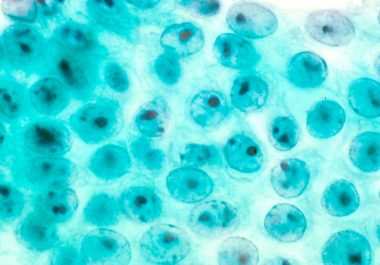

The FDA has approved a new targeted radiotherapeutic for treating two rare neuroendocrine tumors, pheochromocytomas and paragangliomas. The U.S....